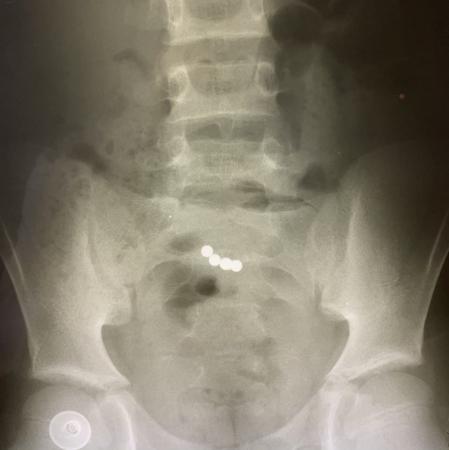

Коломенские хирурги спасли ребенка, проглотившего магнитные шарики

В Коломенскую больницу с рвотой и болями в животе поступил 11-летний ребенок.